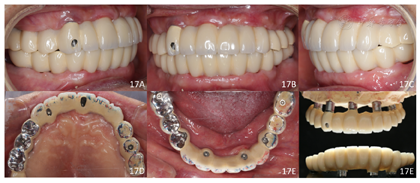

种植修复后1年复查,种植体存留率100%,无修复及机械并发症,咬合关系稳定,获得患者满意的良好咀嚼功能及美学修复效果。

治疗结果:术后3个月全景片显示种植体骨结合良好(图14)。26牙行二期手术,就位复合基台,戴入保护帽。两周后,取下临时修复体,制取上下颌硅橡胶印模,利用临时修复体交叉上

架转移患者颌位关系。设计数字化桥架(图15),切削铝制支架。试戴铝制支架,拍摄全景片显示支架被动就位良好(图16)。按照铝制支架切削纯钛支架,上聚合瓷,患者右侧咬合空间不足,设计金属

面。戴入最终修复体,调合(图17)。种植修复前后面像对比,患者面下1/3高度恢复良好(图18)。

术后一年随访:拍摄全景片显示种植体周围骨结合良好,边缘骨高度稳定(图19)。义齿外形无变化,下颌义齿前牙区舌侧面见牙结石。